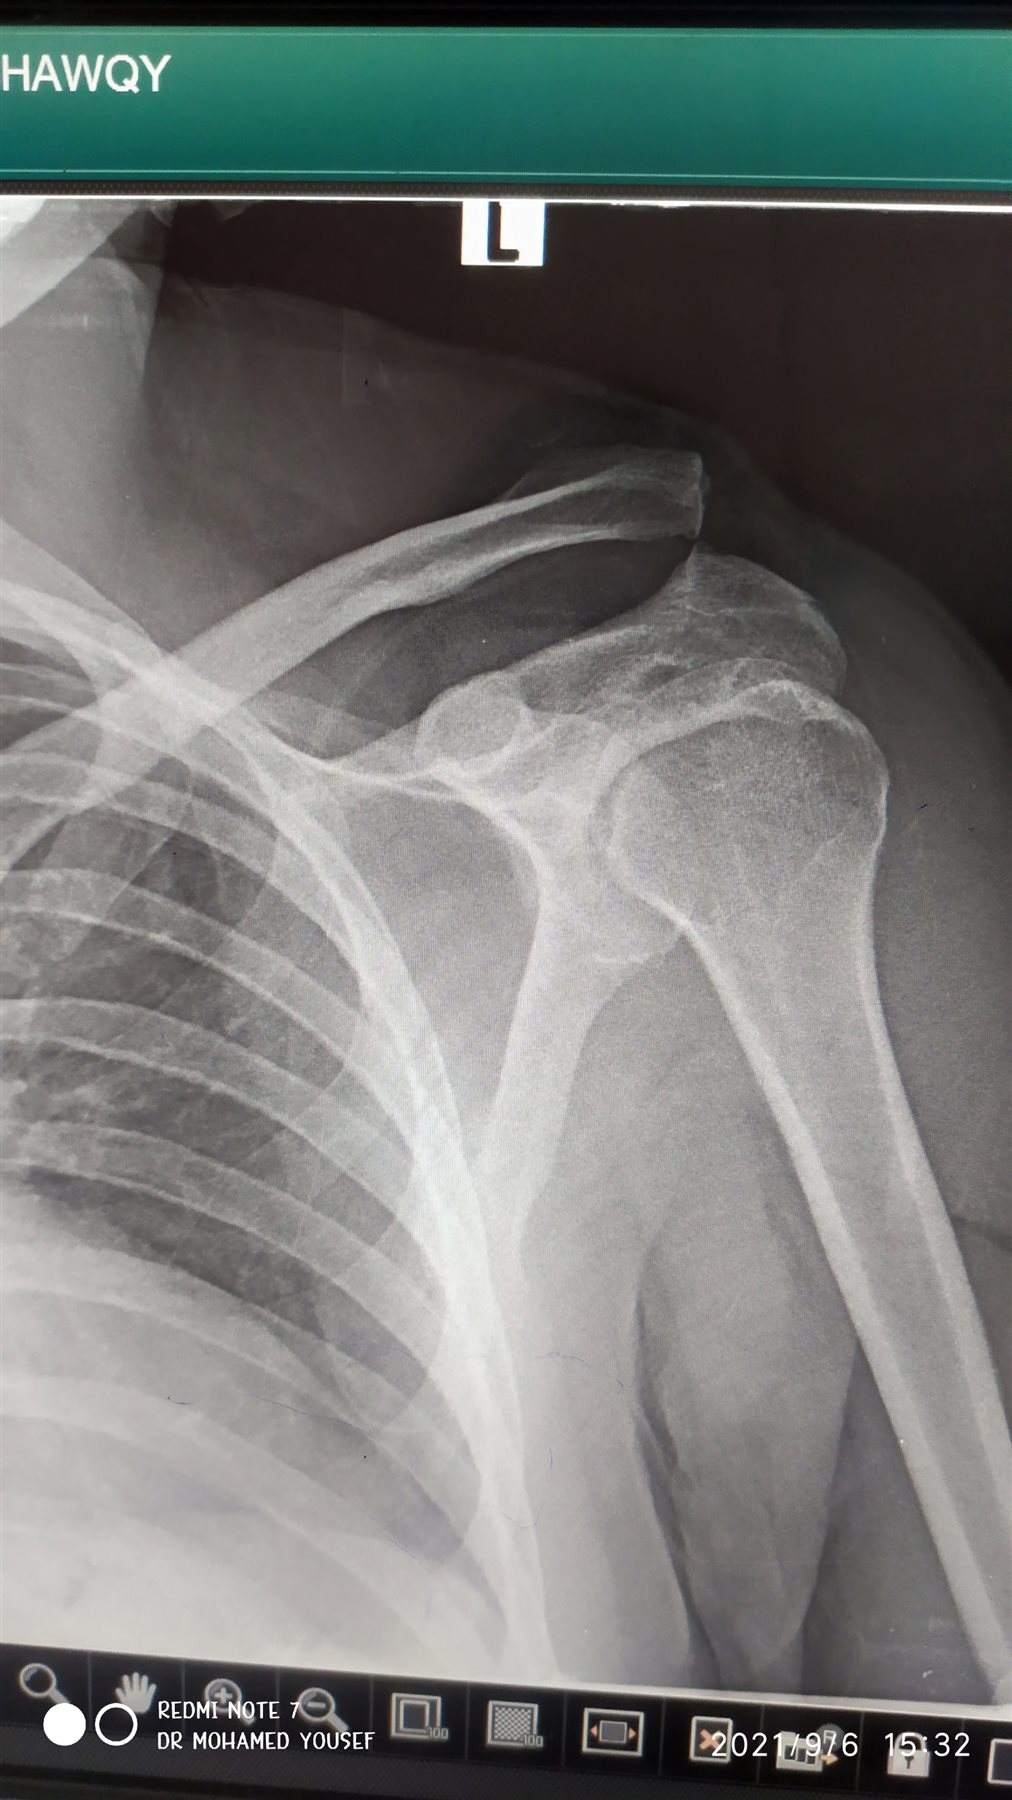

بتقنية جديدة.. نجاح أول عملية تثبيت خلع بمفصل الكتف في "دكرنس العام"

أعلن الدكتور سعد مكي وكيل وزارة الصحة بالدقهلية عن نجاح فريق طبي بإجراء أول عملية تثبيت خلع بمفصل الكتف بتقنية جديدة بمستشفى دكرنس العام لمريض يبلغ من العمر 40 عامًا.

وأوضح وكيل صحة الدقهلية أن التقنية الجديدة تقلل من آلام ما بعد الجراحة لدى المريض، وتحقق التعافي السريع وهي أفضل من الناحية التجميلية، كما أنها لا تستدعي إجراء عملية أخرى لإزالة الشرائح والمسامير المعدنية.